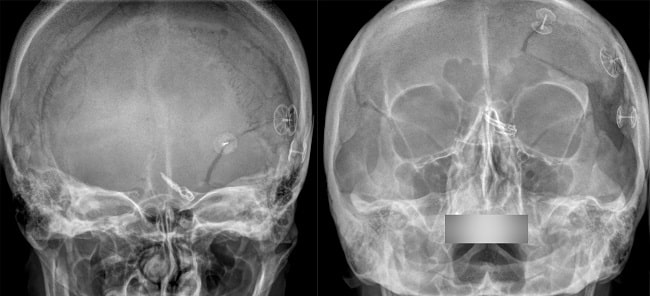

Aneurisma otak atau aneurisma serebral adalah dilatasi abnormal pembuluh darah otak yang membesar serta berisiko mengalami ruptur sewaktu-waktu, sehingga dapat menyebabkan perdarahan subarachnoid atau intrakranial.

Aneurisma otak seringkali terjadi pada area sekitar bifurkasio (percabangan pembuluh darah besar). Hal ini karena struktur pembuluh darah area sekitar bifurkasio dengan tunika media tipis. Terkadang lamina elastik internalnya terfragmentasi atau bahkan tidak ada sama sekali pada dinding pembuluh darahnya.

Sekitar 85% aneurisma otak terletak pada sirkulasi anterior sirkulus Willisi. Namun, aneurisma yang terletak pada sirkulasi posterior memiliki risiko ruptur yang lebih besar.[1,4]